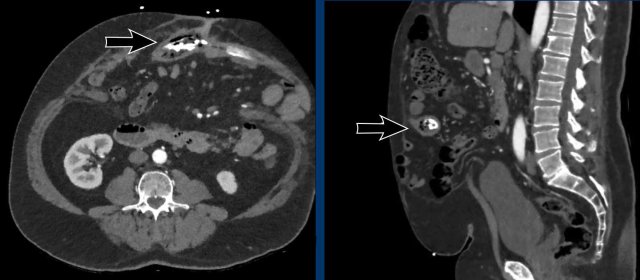

This is another example of a closed loop obstruction within the hernia sac.

The white arrow indicates the first obstruction, where the bowel enters the closed loop.

The yellow arrow indicates the exit.

In this case the closed loop is caused by adhesions within the hernia sack.

Notice the fat infiltration and the dilated loops with slightly hyperdense walls.

These are all signs of bowel ischemia.

Immediate laparotomy was performed.

The bowel within the hernia sac was ischemic and had a purple color, but after cleavage of the adhesions, the color of the bowel returned to normal.